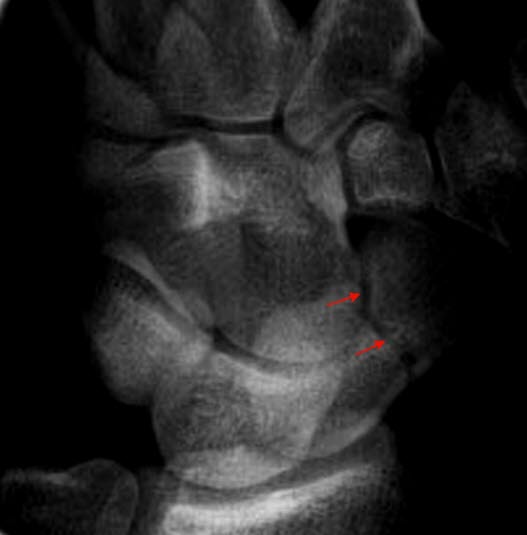

Tverrfraktur gjennom os scaphoideum (pil)

Slike frakturer kan være vanskelig å se akutt, og medfører ofte pseudartrose ubehandlet